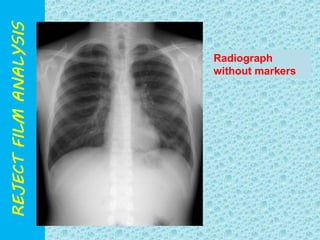

Radiograph

without markers

wrongly

placed

Marker